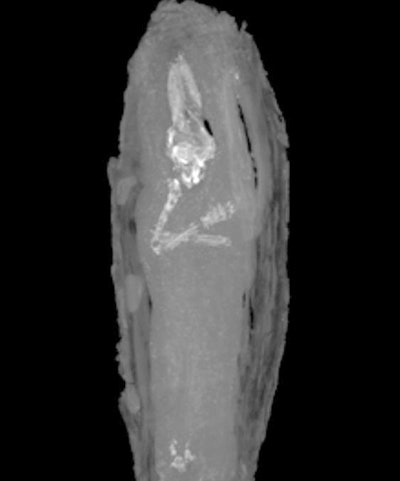

The wood casket was covered with tiny carvings, and held a small package wrapped in bandages and covered with black resin. After an x-ray of the coffin gave inconclusive results suggesting a skeleton, the results of cross-sectional CT clearly showed the remains of a fetus.

The fetus had 10 fingers and 10 toes, and long leg and arm bones; however its gender cannot be determined. The skull and pelvis were found to be collapsed. The value of CT is it can show the inner workings of such artifacts without causing any structural damage, enabling the research team to check for abnormalities and estimate the age as accurately as possible, said Dr. Tom Turmezei, an honorary consultant radiologist at Addenbrooke's Hospital in Cambridge. He said the tiny fetus, estimated to be aged at 16 to 18 weeks' gestation, was CT's most valuable find yet at the hospital.